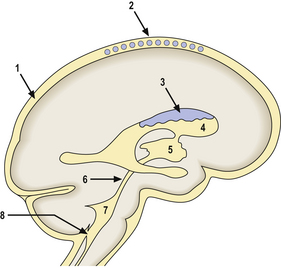

Herniations occur at several characteristic sites within the cranial cavity, depending on the site of the space-occupying lesion (Fig. 26.5). Transtentorial herniation is frequently fatal because of secondary haemorrhage into the brainstem (Fig. 26.6). This is a common mode of death in patients with large intrinsic neoplasms or intracranial haemorrhage.

image

Fig. 26.5 Sites of intracranial herniation. Space-occupying lesions in the cerebral hemispheres may cause herniation of the cingulate gyrus under the falx cerebri (1) or of the hippocampal uncus and parahippocampal gyrus over the tentorium cerebelli (2). Cerebellar tonsillar herniation through the foramen magnum (3) can occur with lesions in the cerebrum or cerebellum. A swollen brain will herniate through any defect in the dura and skull (4).